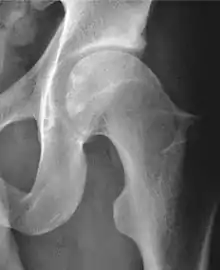

X-ray

Projectional radiography ("X-ray")is often considered first line for FAI.[10] Anterior-posterior pelvis and a lateral image of the hip in question should be attained.[10] A 45-degree Dunn view is also recommended.[10][19]